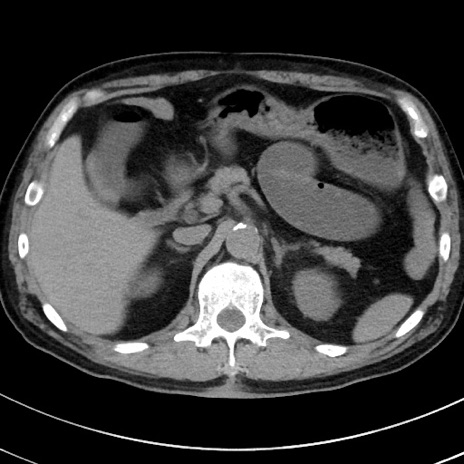

症例38(横断像)

【症例】70歳代 男性

【主訴】腹痛・嘔吐

【現病歴】昨晩より、嘔吐・腹痛あり。今朝になっても嘔吐あり。来院。

【既往歴】心臓バイパス手術、開腹胆摘、腸閉塞

【身体所見】BP 107/71mmHg、HR 116/min、腹部:平坦、軟、下腹部に軽度圧痛あり。反跳痛なし。

【データ】WBC 15100、CRP 0.32